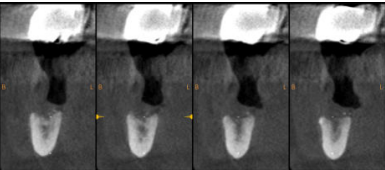

Se presenta el caso de un paciente varón de 73 años, que en octubre de 2017 acudió a la consulta refiriendo una hipoestesia del hemilabio inferior derecho, precedida de una anestesia hemilabial, asociada a la colocación de implantes osteointegrados en el cuarto cuadrante dos años atrás. Su estado de salud general es bueno y no es fumador. Durante la exploración intraoral se observó movilidad de grado II en el diente 45 y la exposición de las espiras de los implantes correspondientes a los dientes 46 y 47, además de supuración a la palpación de la zona. En la exploración radiológica, mediante radiografía panorámica, se evidenció una gran pérdida ósea alrededor de ambos implantes que también afectaba al diente 45 y se observó la invasión del conducto del nervio dentario inferior por el ápice de los implantes. Asimismo, se realizó una tomografía computarizada de haz cónico (CBCT), que confirmó la presencia de los ápices de ambos implantes en el conducto nervioso (Figura 1).